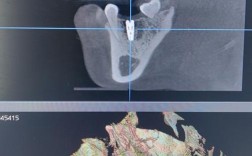

- CBCT(锥形束CT): 这是现代种植牙术前评估的“金标准”,提供三维立体影像,精确测量缺牙区牙槽骨的骨量(高度、宽度、厚度)、骨密度、评估骨缺损情况,并精确定位重要的神经、血管、上颌窦等解剖结构,为种植体的位置、角度、长度设计提供关键依据。